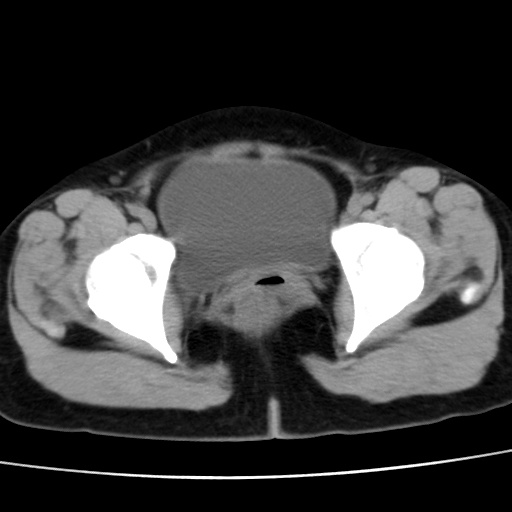

考虑多发子宫肌瘤,子宫直肠窝双囊性占位,另直肠周围脂肪密度增高,不知有何病史

子宫肌瘤,宫体部后方见液性密度影,是肠道还是子宫与直肠陷窝积液不好说,我觉得它的位置有点高

患者发热,而子宫直肠窝液性灶有明显边缘且局限且囊性,不除外为包裹性积液或脓肿

1)考虑子宫肌瘤可能性大。2)子宫后方囊性占位性病变,不排除卵巢囊肿可能。

考虑多发子宫肌瘤。子宫后方囊性占位性病变,不排除卵巢囊肿可能。